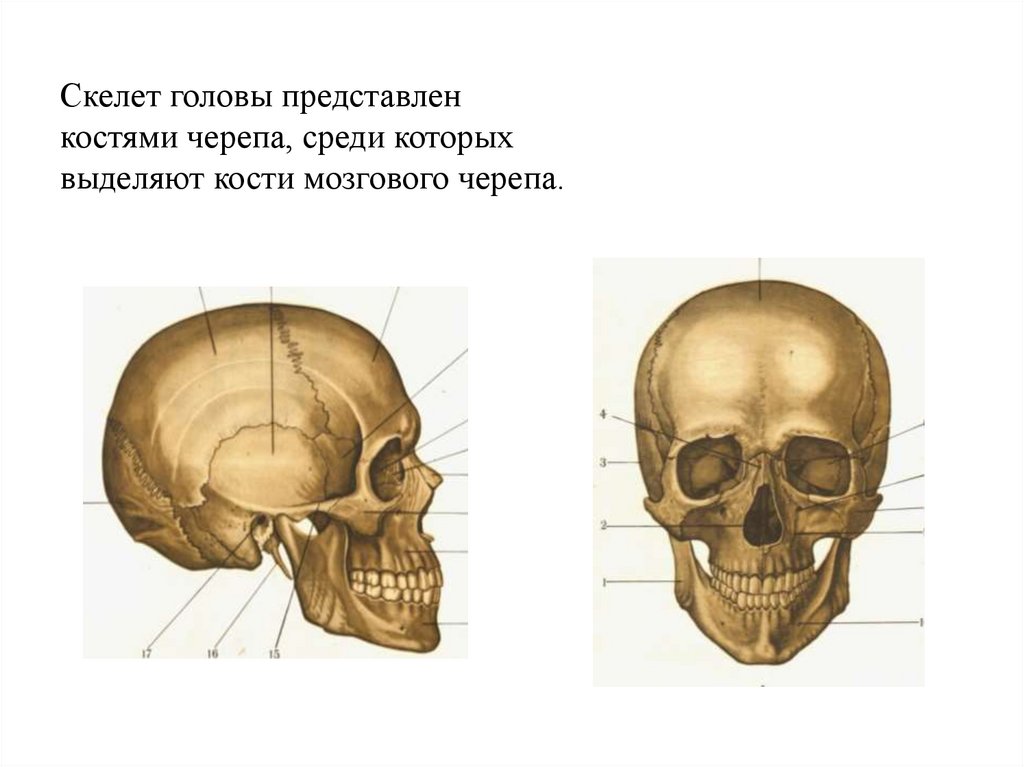

Анатомические изображения срединной сагиттальной линии черепа